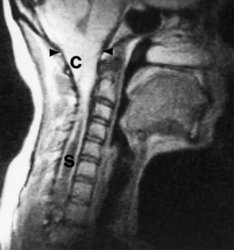

SYRINGOMYELIA

Syringomyelia is an uncommon condition in which a cavity (syrinx) develops within the spinal cord, sometimes extending up into the brainstem (syringobulbia). The cavity is usually situated in the central region of the cord, posterior to the central canal. Syringomyelia occurs most frequently in the cervical region of the cord, and usually extends for several centimetres in a vertical direction. However, extensive cavities involving almost the entire length of the cord have been described. Modern radiological techniques are of great value in delineating the extent of the lesion (see Fig. 26.22).

Syringomyelia can arise in a variety of conditions, which may be considered as follows:

maldevelopment of the cord, with failure of fusion of the ventral and dorsal segments

disorders of CSF flow, where CSF is propelled down the central canal

tissue destruction following a spinal cord injury, or as a consequence of an intrinsic neoplasm.

The cavities within the spinal cord in syringomyelia are lined by reactive astrocytes and their fibrillary processes. The CSF composition in syringomyelia is normal.

The clinical manifestations of syringomyelia usually occur in adult life, with:

lower motor neurone lesion (muscle weakness and atrophy) in upper limbs due to compression of anterior horn cells

dissociated anaesthesia (loss of pain and temperature sensation) due to damage to nerve fibres crossing the cord in the lateral spinothalamic tracts.

Surgery can sometimes arrest or alleviate symptoms by decompression or draining the fluid in the cystic cavity.